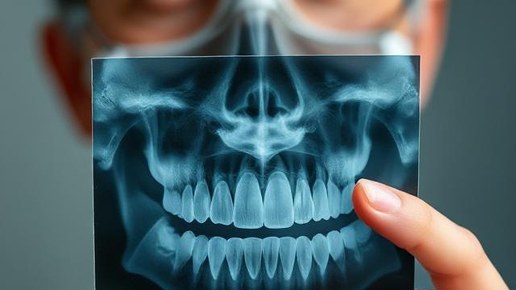

Да, такие истории, увы, не редкость. Но на самом деле удаление зубов мудрости – лишь в половине случаев действительно сложная процедура. Прорезываются самые дальние зубы поздно и в процессе доставляют массу неудобств. Из-за этого многие пациенты боятся их удалять, и планово, и по показаниям, когда уже трудно терпеть боль. Но спешим заверить, при всей сложности процедуры для пациентов, для врача она – самая рядовая. Сегодня удалять зубы мудрости не больно, а лишь немного страшно 😄. Расскажем, как...